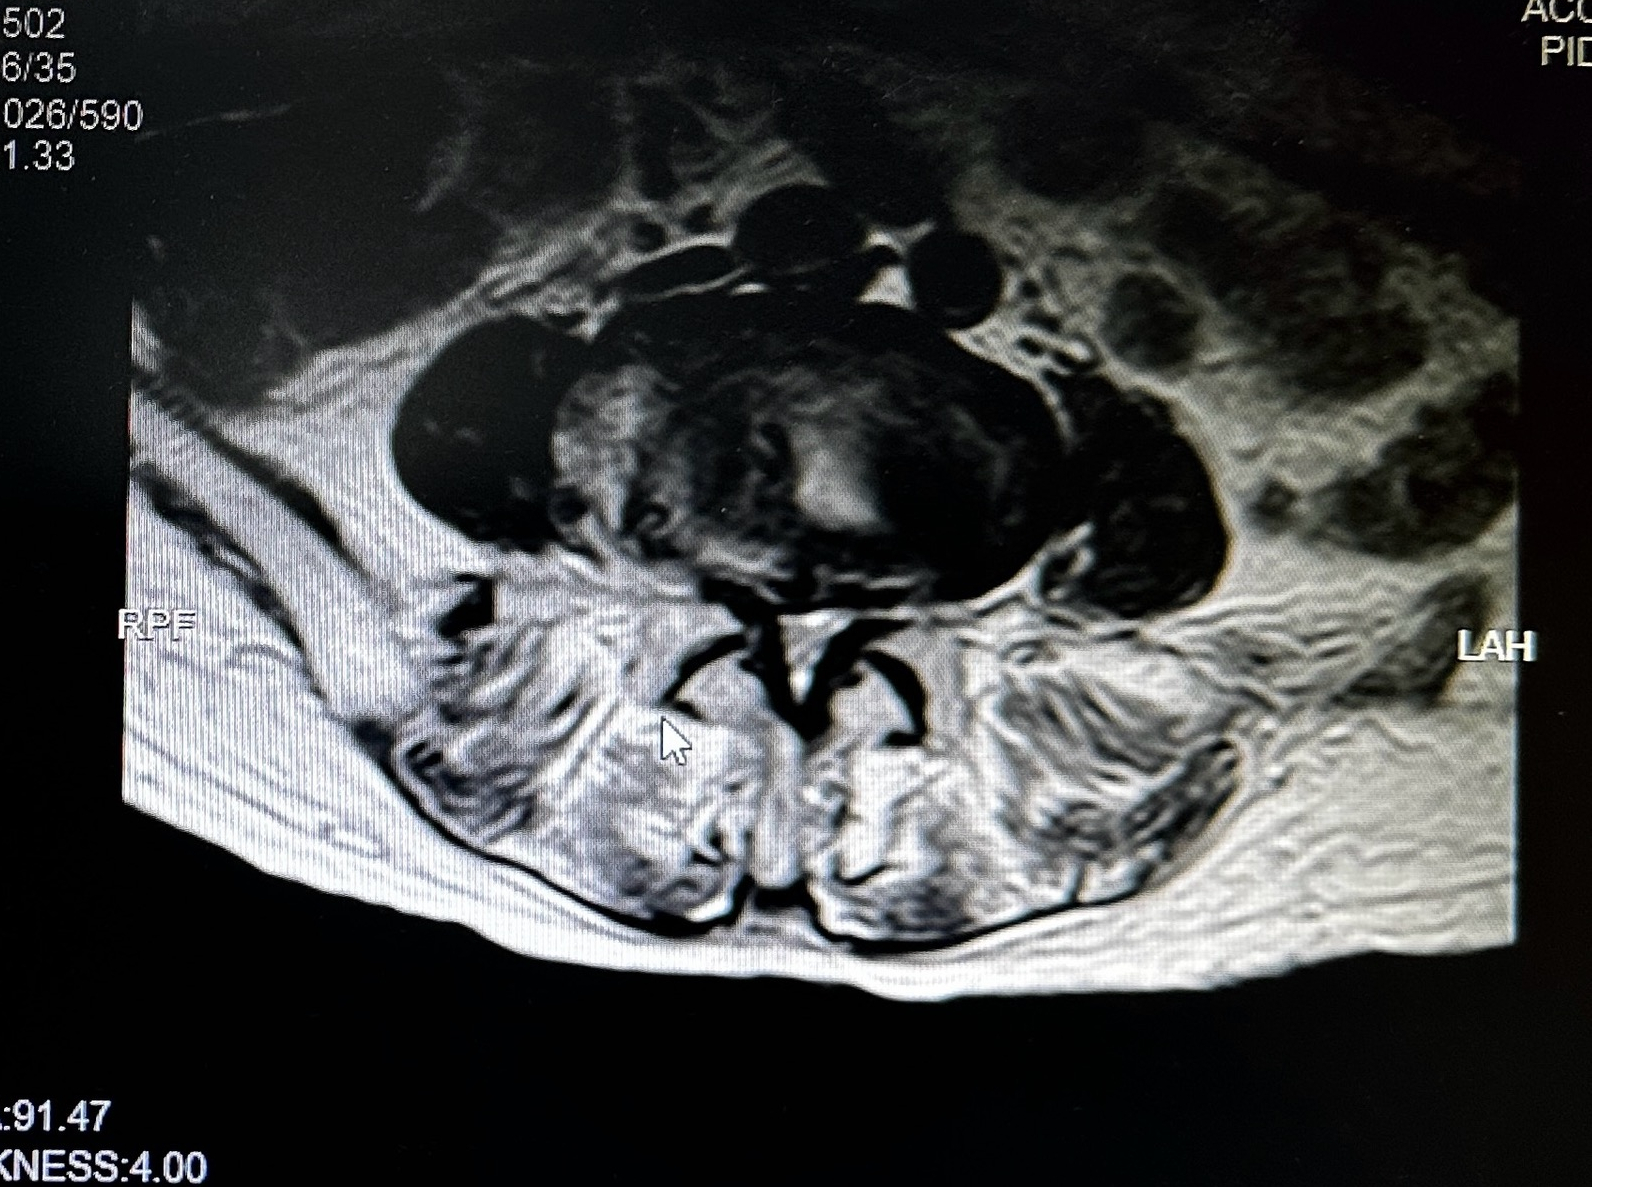

术前MRI片:严重腰椎椎管狭窄

我院副院长、骨科主任张勇华及省人医帮扶专家陈崇博士充分讨论病情后,考虑到徐婆婆为高龄老人,身体条件较差,同时合并腔隙性脑梗、高血压、重度骨质疏松、心肺功能异常等内科疾病,常规开放手术围术期风险较大,患者也不接受开放手术,采用脊柱内镜进行微创减压是非常好的治疗选择。

UBE技术(unilateral biportal endoscopy)是指单边双通道内镜下的脊柱手术,是一项新兴的微创技术,在脊柱疾病的治疗中疗效确切。UBE技术适用于各类型的间盘突出病例,尤其适用于复杂椎间盘突出、椎管狭窄、腰椎滑脱、胸椎管狭窄、脊柱翻修病例等复杂病例的内镜微创治疗,具有术中时间短、创伤小、术后康复快、效果显著等优势。